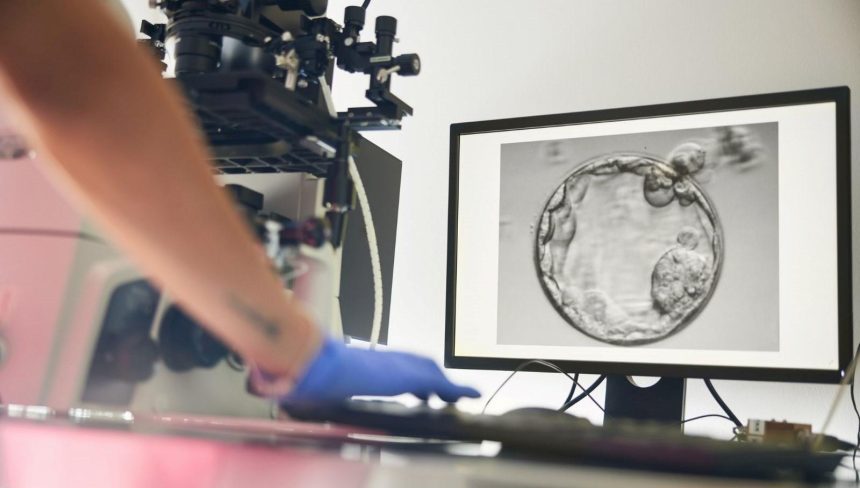

Ancak üretilen yumurtaların sadece yüzde 9’undan daha azı, döllenme sonrası embriyo gelişiminin kritik etabı olan blastosist evresine (5–6 günlük gelişim) ulaşabildi. Üstelik ortaya çıkan tüm embriyolar kromozom bozuklukları taşıyordu.